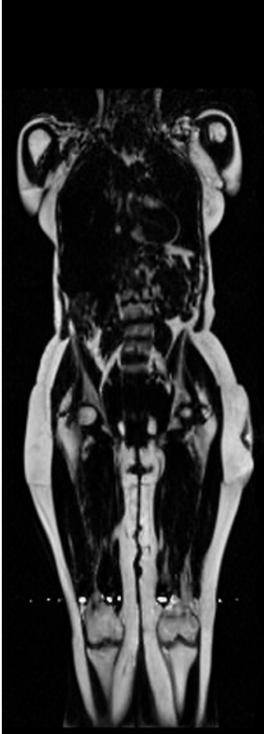

Notably, X-Diffusion achieves state-of-the-art dB for a few input slices while baselines require more than 60 input slices to achieve similar performance (Figure 7). The margin is more than 12 dB PSNR for the 1-slice input in both the BRATS and the UK Biobank benchmarks (see Table 1 and Figure 6). For reference, two randomly sampled MRIs from UK Biobank would have a PSNR of 15.95 dB 0.36 (on 4800 randomly sampled examples). Omitting the preprocessing step of alignment DXA to MRI, leads to a drop of PSNR on average by 2.87 dB (29.01 dB 26.14 dB). The slices from 3D reconstructed volumes at varying depths and axis of rotation, visually match the ground truths for both brain and whole-body scans (see Figures 4 and 5 left). We also plot the error map (Figure 3) and the spread of the error (Figure 5 right) of such X-Diffusion generations to highlight the differences with the ground truth MRIs.

Preservation of Spine Curvature. For the spine segmentation on UK Biobank, we use a UNet++ model [83] with Dice Loss. We use a model trained to predict curves on DXA on UK Biobank [11]). We measure the Pearson correlation factor [11] of spine curvature measured on the generated MRIs where the input is a single MRI coronal slice, a single sagittal slice, or from the paired DXA, against the curvature of reference real MRIs of the same samples. The correlation coefficients are 0.89 for the coronal MRIs, 0.88 for the sagittal MRIs, and 0.87 for the DXAs on the test set of 308 human-annotated angles. We can then bin the curvature of the spines under different scoliosis categories based on human-annotated angles: mild: , moderate: , and severe . We show the results in Figure 8. This illustrates that the generated MRIs preserve the spine curvature from normal to severe scoliosis cases. Additional details about spine curvature are provided in supplementary material.